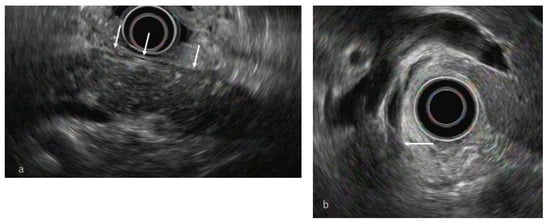

3.3.1. Conventional EUS

- Hoki, N.; Mizuno, N.; Sawaki, A.; Tajika, M.; Takayama, R.; Shimizu, Y.; Bhatia, V.; Yamao, K. Diagnosis of autoimmune pancreatitis using endoscopic ultrasonography. J. Gastroenterol. 2009, 44, 154–159. [Google Scholar] [CrossRef]

- Farrell, J.J.; Garber, J.; Sahani, D.; Brugge, W.R. EUS findings in patients with autoimmune pancreatitis. Gastrointest. Endosc. 2004, 60, 927–936. [Google Scholar] [CrossRef]

- Okabe, Y.; Ishida, Y.; Kaji, R.; Sugiyama, G.; Yasumoto, M.; Naito, Y.; Toyonaga, A.; Tsuruta, O.; Sata, M. Endoscopic ultrasonographic study of autoimmune pancreatitis and the effect of steroid therapy. J. Hepatobiliary Pancreat. Sci. 2012, 19, 266–273. [Google Scholar] [CrossRef] [PubMed]